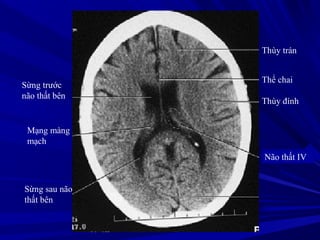

Liềm não

Trung tâm bán

bầu dục

Thùy trán

Thể chai

Thùy đính

Não thất IV

Sừng trước

não thất bên

Sừng sau não

thất bên

Mạng màng

mạch